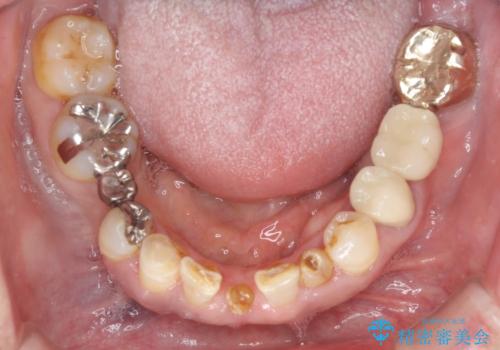

- 乳歯や矮小歯が多くある前歯部の審美障害が気にして来院された患者様です。

上顎の矮小歯は隙間が多く、歯軸の傾斜も大きかったため、部分矯正により補綴治療前に歯の位置を整えることとしました。

下顎の乳歯は支台歯として機能することは困難と思われたので、事前に抜歯をし、上顎の矯正治療終了のタイミングに合わせて、セラミックブリッジにて補綴治療することとしました。

前歯部はディープバイトという、上顎前歯が下顎前歯に深く覆い被さる咬合であったので、理想的には全顎矯正が必要となりますが、今回は患者希望により前歯部のみの部分矯正で対応しました。そのため下顎犬歯の神経を取り除くことになってしまったのは心残りであります。